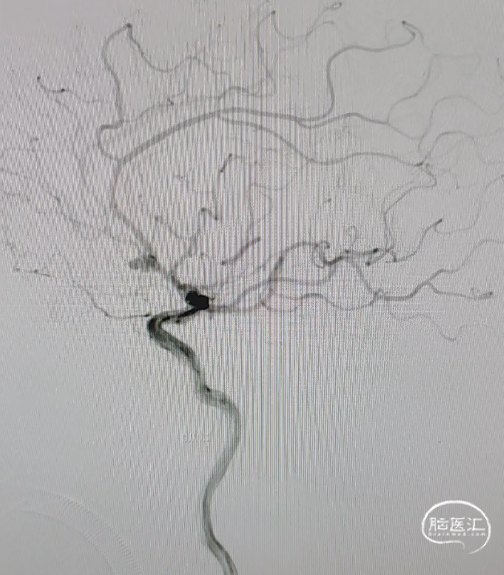

术后3个月随访,各分支血管血流通畅,动脉瘤不再显影。

术后3个月随访,动脉瘤已被完全修复。